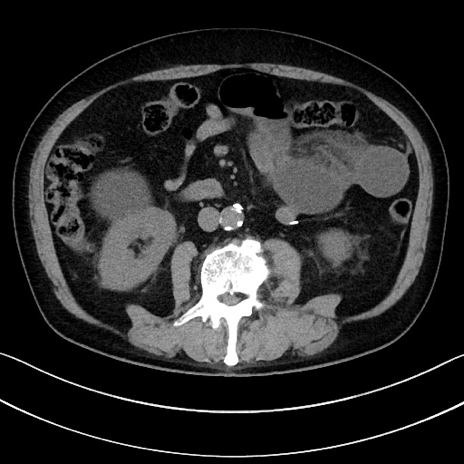

症例15(横断像)

【症例】70歳代男性

【主訴】腹痛

【現病歴】今朝から腹痛あり。全体的に痛い。特に左上の方。排ガスが今日はない。冷や汗が出る。

【既往歴】直腸癌術後

【身体所見】左側腹部〜上腹部に圧痛あり。腹膜刺激症状明らかなではない。軽度反跳痛。左下腹部に術後瘢痕あり。

【データ】WBC 7700、CRP 0.02